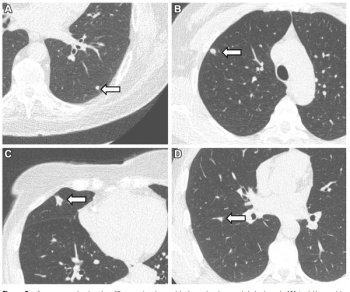

Utilizing low-dose computed tomography (CT) scans for a cohort of over 10,000 non-smokers, researchers found that over 11 percent of study participants had clinically relevant lung nodules.

New research shows the use of adjunctive AI resulted in a 12 percent higher sensitivity rate for lung nodule detection in comparison to radiologists without AI.